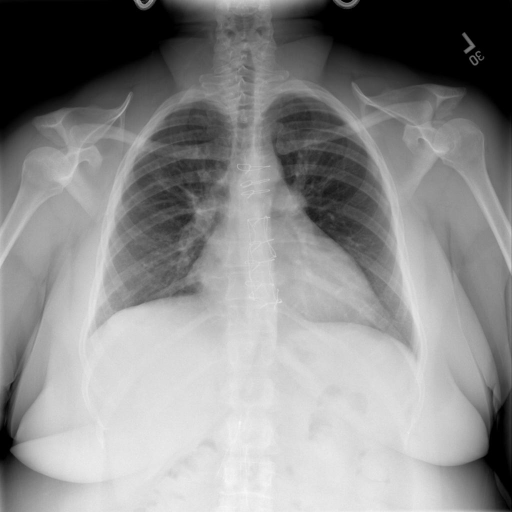

# 本文贡献  - 借助ChatGPT以及公开的数据集,我们构造了一个`X光影像-诊断报告`对的医学多模态数据集; # 数据集 - [MIMIC-CXR](https://physionet.org/content/mimic-cxr-jpg/2.0.0/)是一个公开可用的胸部X光片数据集,包括377,110张图像和227,827个相关报告。 - [OpenI](https://openi.nlm.nih.gov/faq#collection)是一个来自印第安纳大学医院的胸部X光片数据集,包括6,459张图像和3,955个报告。 在上述工作中,报告信息都为非结构化的,不利于科学研究。为了生成合理的医学报告,我们对两个数据集进行了预处理,并最终得到了可以用于训练的**英文报告**。除此之外,为了更好的支持中文社区发展,借助ChatGPT的能力,我们将英文报告进行了中文翻译,并最终形成了可用于训练的数据集。 |数据集|数量|下载链接| |:-|:-|:-| |MIMIC-CXR-zh|-|-| |OpenI-zh|6,423|[诊疗报告](./data/Xray/openi-zh.json) 、[X光影像](https://pan.baidu.com/s/13GBsDMKf6xBZBSHpoWH_EA?pwd=k9sh)| # 快速上手 1. 安装环境 ```bash # 安装依赖 pip install -r requirements.txt # 国内换源安装依赖 pip install -i https://mirrors.aliyun.com/pypi/simple/ -r requirements.txt ``` 此时默认会安装`deepspeed`库(支持`sat`库训练),此库对于模型推理并非必要,同时部分`Windows`环境安装此库时会遇到问题。 如果想绕过`deepspeed`安装,我们可以将命令改为: ```bash # 安装依赖 pip install -i https://mirrors.aliyun.com/pypi/simple/ -r requirements_wo_ds.txt # 安装SwissArmyTransformer pip install -i https://mirrors.aliyun.com/pypi/simple/ --no-deps "SwissArmyTransformer>=0.3.6" ``` 2. 模型推理 CLI推理: ```python python cli_demo.py --from_pretrained checkpoints/finetune-XrayGLM-05-25-01-04 --prompt_zh '详细描述这张胸部X光片的诊断结果' ``` 更多[参数](https://github.com/WangRongsheng/XrayGLM/blob/main/cli_demo.py#L16) # 效果展示 |X光影像|诊疗报告(医生)|XrayGLM| |:-|:-|:-| ||根据X射线图像,心脏大小正常,肺部看起来很清晰。已经排除了肺炎、积液、水肿、气胸、腺病、结节或肿块的存在。该发现表明一切正常。换句话说,总体印象是胸部正常。|X光片显示,心脏大小正常。肺部没有气胸或胸腔积液的证据。骨骼结构看起来没有任何异常。总的来说,X光片表明没有发现急性心肺疾病的迹象。| ||X光图片显示没有扭曲的区域、可疑的骨质不透明度或胸腺积液。心脏大小轻微增大,但非常稳定。此外,没有气胸的证据,肺野也正常。总体来说,X光片显示没有急性心脏异常,但要注意轻微的心脏扩大。|X光片显示,心脏大小正常。肺部和纵隔轮廓清晰,没有气胸或胸腔积液的证据。骨骼结构完整,没有任何急性异常。| ||心影形态在正常范围内。没有急性骨质异常。有可能出现没有明显的吸水或肺实质状况的线索。没有大面积积液或气胸。有可能怀疑其有误吸或肺实质问题。为了确诊和治疗,可能需要进行适当的影像学随访。|心脏大小正常,肺部和纵隔轮廓清晰。没有急性异常或活动受限的证据。没有任何明显的气胸、胸腔积液或肺不张的迹象。此外,也没有发现任何局灶性骨质异常或其他急性疾病。| # 项目致谢 1. [VisualGLM-6B](https://github.com/THUDM/VisualGLM-6B)为我们提供了基础的代码参考和实现; 2. [MiniGPT-4](https://github.com/Vision-CAIR/MiniGPT-4)为我们这个项目提供了研发思路; 3. ChatGPT生成了高质量的中文版X光检查报告以支持XrayGLM训练; 4. [gpt_academic](https://github.com/binary-husky/gpt_academic)为文档翻译提供了多线程加速; 5. [MedCLIP](https://github.com/RyanWangZf/MedCLIP) 、[BLIP2](https://huggingface.co/docs/transformers/main/model_doc/blip-2) 、[XrayGPT](https://github.com/mbzuai-oryx/XrayGPT) 等工作也有重大的参考意义;  这项工作由[澳门理工大学应用科学学院](https://www.mpu.edu.mo/esca/zh/index.php)硕士生[王荣胜](https://github.com/WangRongsheng) 、[段耀菲](https://github.com/IsBaSO4) 、[李俊蓉](https://github.com/lijunrong0815)完成,同时这项工作受到[檀韬](https://scholar.google.com/citations?hl=zh-CN&user=lLg3WRkAAAAJ)副教授、[彭祥佑](http://www.patrickpang.net/)老师的帮助支持。 *特别鸣谢:[USTC-PhD Yongle Luo](https://github.com/kaixindelele) 提供了有3000美金的OpenAI账号,帮助我们完成大量的X光报告翻译工作 # 免责声明 本项目相关资源仅供学术研究之用,严禁用于商业用途。使用涉及第三方代码的部分时,请严格遵循相应的开源协议。模型生成的内容受模型计算、随机性和量化精度损失等因素影响,本项目无法对其准确性作出保证。即使本项目模型输出符合医学事实,也不能被用作实际医学诊断的依据。对于模型输出的任何内容,本项目不承担任何法律责任,亦不对因使用相关资源和输出结果而可能产生的任何损失承担责任。 # 项目引用 如果你使用了本项目的模型,数据或者代码,请声明引用: ```bash @misc{wang2023XrayGLM, title={XrayGLM: The first Chinese Medical Multimodal Model that Chest Radiographs Summarization}, author={Rongsheng Wang, Yaofei Duan, Junrong Li, Patrick Pang and Tao Tan}, year={2023}, publisher = {GitHub}, journal = {GitHub repository}, howpublished = {\url{https://github.com/WangRongsheng/XrayGLM}}, } ``` # 使用许可 此存储库遵循[CC BY-NC-SA](https://creativecommons.org/licenses/by-nc-sa/4.0/) ,请参阅许可条款。